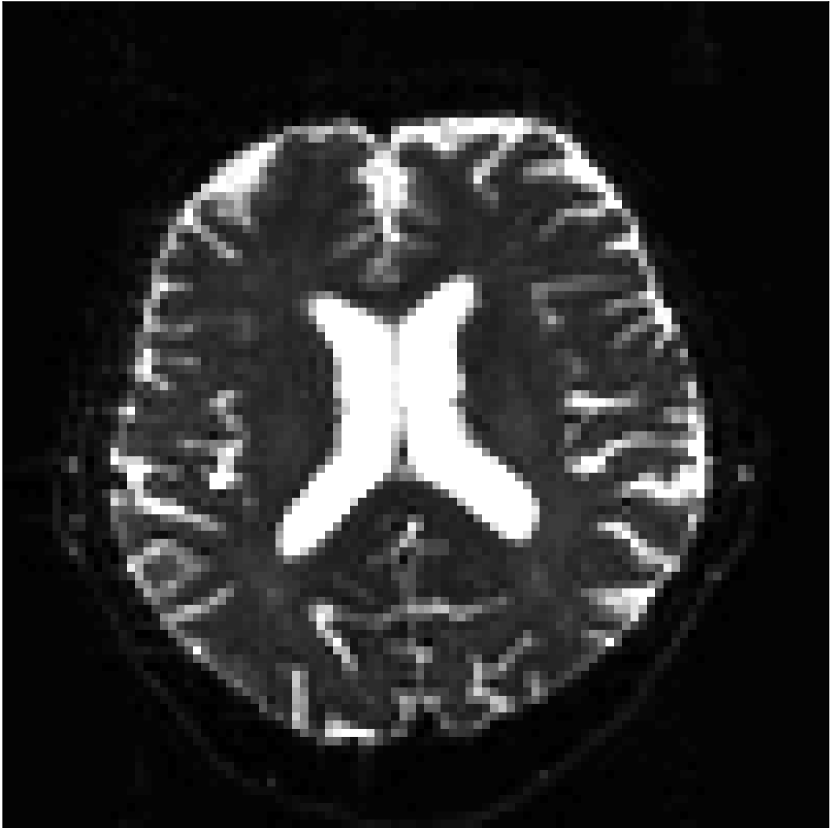

Figure 10 compares mean diffusivity maps across various partial Fourier factors between the CCNN and state-of-the-art methods.

No PF

7/8 PF

6/8 PF

5/8 PF

SoA

Refer to caption

MD, μ𝜇\mum2/ms

CCNN

Figure 10: Comparison of mean diffusivity (MD) parameter maps across PF factors of 5/8ths, 6/8ths, 7/8ths, and without PF (No PF). The methods include state-of-the-art (SoA) and CCNN methods. Without partial Fourier, both methods are similar; however, as the PF factor increases, substantial artifacts are introduced in the SoA method, particularly around the lateral ventricles. The CCNN method is able to reduce the introduction of artifacts.

The methods perform similarly without partial Fourier acceleration, but as partial Fourier acceleration increases, the image is continually degraded in the SoA method, with "black voxels" appearing around the lateral ventricles. The CCNN method mitigates the appearance of these artifacts in the parameter maps.